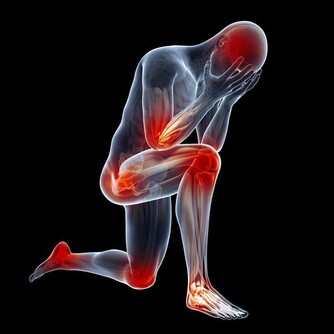

痛風患者中久坐少動的腦力勞動者多,體力勞動者少。因為運動能促進新陳代謝,幫助降血脂及控制血糖、血尿酸。但是,運動不當也會誘發痛風,如果已有高尿酸血症,突然大量的運動可以誘發痛風急性發作。

加班熬夜對於許多年輕人來說不可避免,但過度勞累可使人體自主神經調節紊亂,

易致體表及內臟血管收縮,包括腎血管的收縮,從而引起尿酸排泄減少。

如果長時間緊張工作,過度疲勞,就有可能誘發痛風。